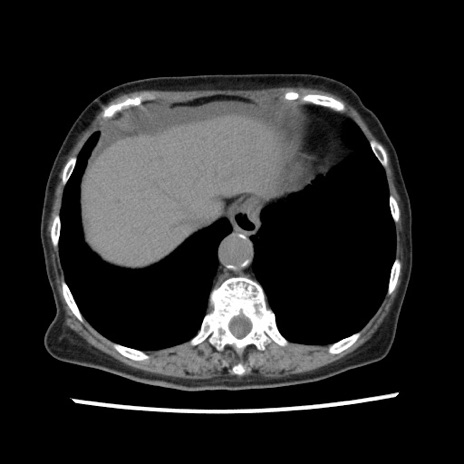

矢状断像